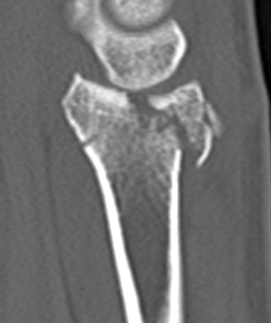

Dorsal ulna / volar ulna

Distal Radius Volar and Dorsal Ulna FragmentsDistal Radial Fracture CTDistal radius volar ulnar fracture

Distal Radius Dorsal Ulna FragmentDRUJ FractureDistal Radius Radioulna Fragments